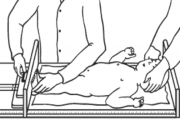

| 05:44, 19 באוגוסט 2014 | מדידת אורך בתינוק.png (קובץ) |  |

148 קילו־בייטים | Motyk | 1 | |